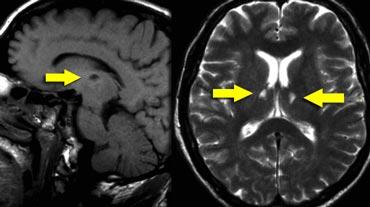

Các hình ảnh cho thấy bệnh nhân có nhồi máu PCA chiến lược liên quan đến hồi hải mã.

Loại nhồi máu này có thể dẫn đến sa sút trí tuệ đột ngột nếu nằm ở bán cầu ưu thế.

Thường sẽ không dẫn đến sa sút trí tuệ nếu xảy ra ở bán cầu không ưu thế.

Các nhân trong của đồi thị đóng vai trò quan trọng trong trí nhớ và học tập.

Nhồi máu một bên lớn hoặc nhồi máu hai bên ở vùng này có thể gây sa sút trí tuệ.

Cần chú ý đặc biệt đến các vùng này để phát hiện những ổ nhồi máu nhỏ này.

Trên hình ảnh FLAIR, bạn sẽ dễ dàng bỏ sót các ổ nhồi máu này, vì chúng có thể đồng tín hiệu với các cấu trúc xung quanh (8).

Cần có chuỗi xung T2W độ phân giải cao để phát hiện các ổ nhồi máu đồi thị này.

FLAIR ở vùng dưới lều tiểu não và tủy sống có giá trị hạn chế vì nó không chỉ ức chế tín hiệu của nước mà còn ức chế cả bệnh lý có thời gian hồi phục T1 dài.